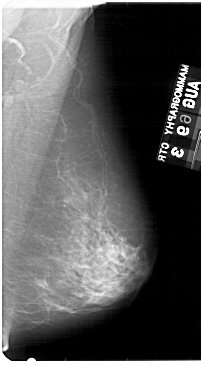

A_1954_1.RIGHT_MLO

RIGHT_MLO LINES 5491 PIXELS_PER_LINE 3001 BITS_PER_PIXEL 12 RESOLUTION 43.5 NON_OVERLAY